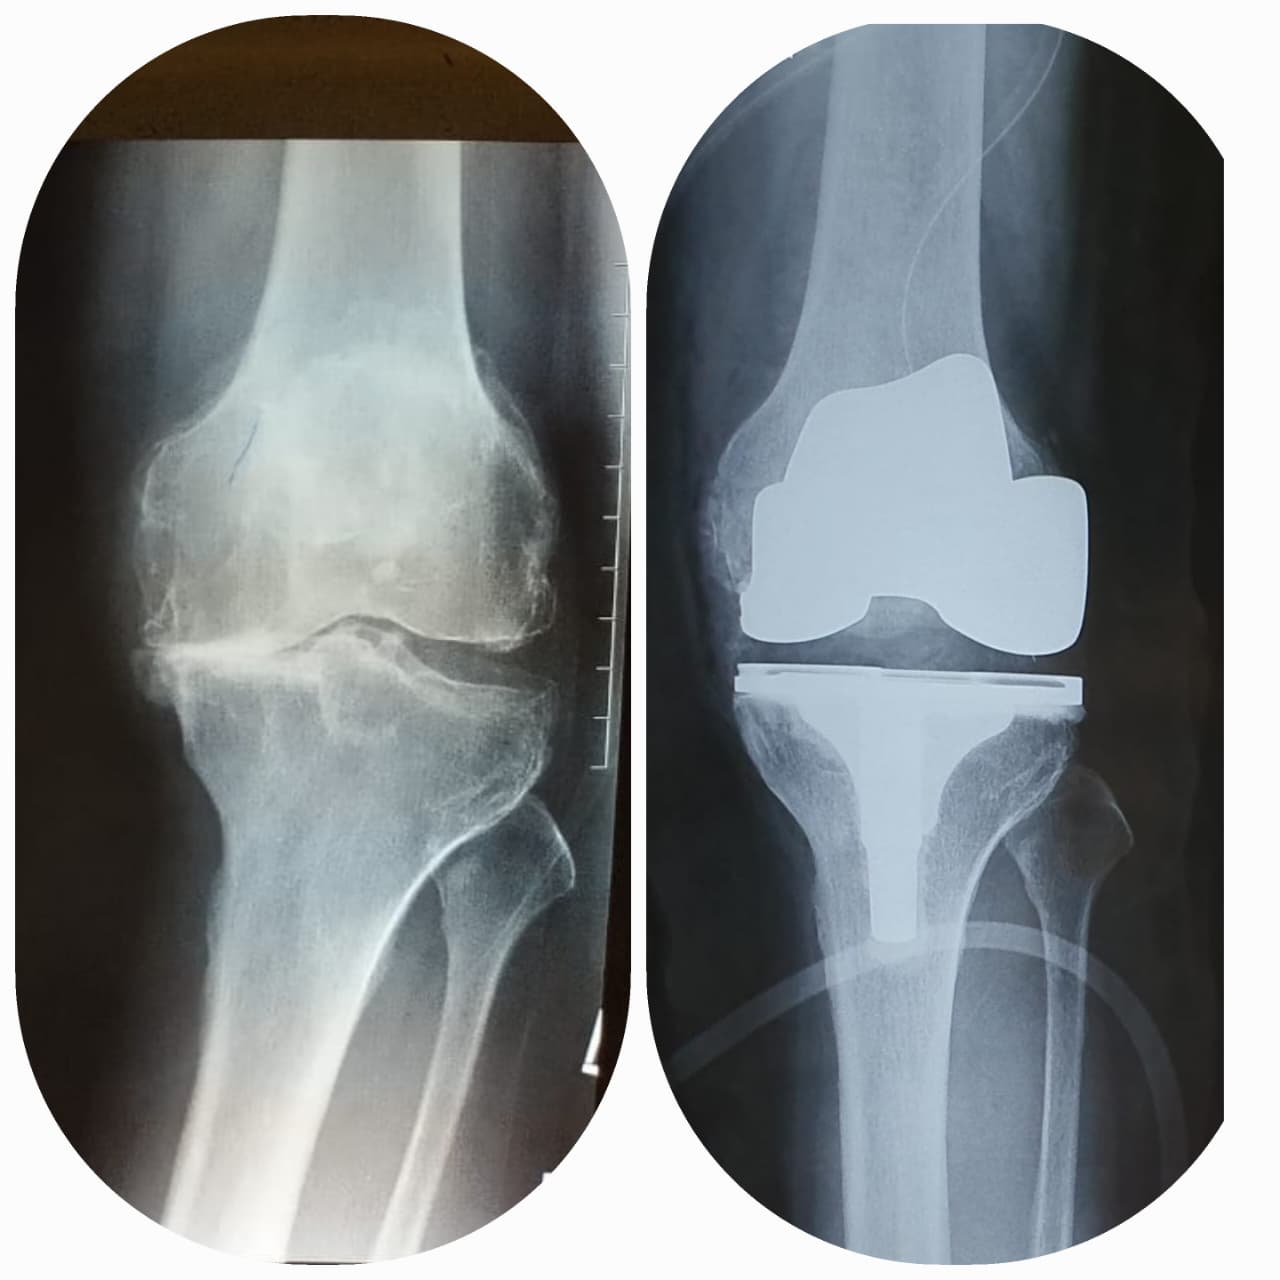

Total knee replacement